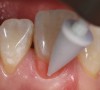

Fig 3. After using a very fine lead pencil to mark the curvilinear nature of the anatomical root area, a small spherical shaped amount of gingival colored composite material was placed on the tooth, light-cured, and used for shade determination with a custom shade tab.

Figure 3

Fig 4. Close-up view showing the pink composite shade estimation on the gingival tissue.

Figure 4